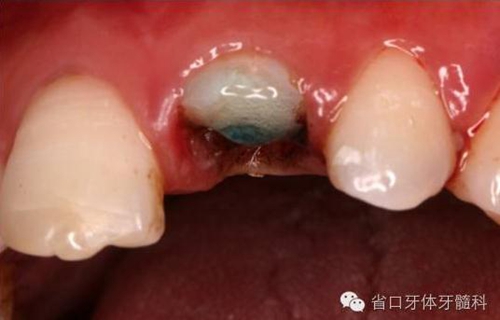

圖2. 術(shù)前口內(nèi)照片,21/冠折。

圖4. 拔除斷冠后的唇面照片